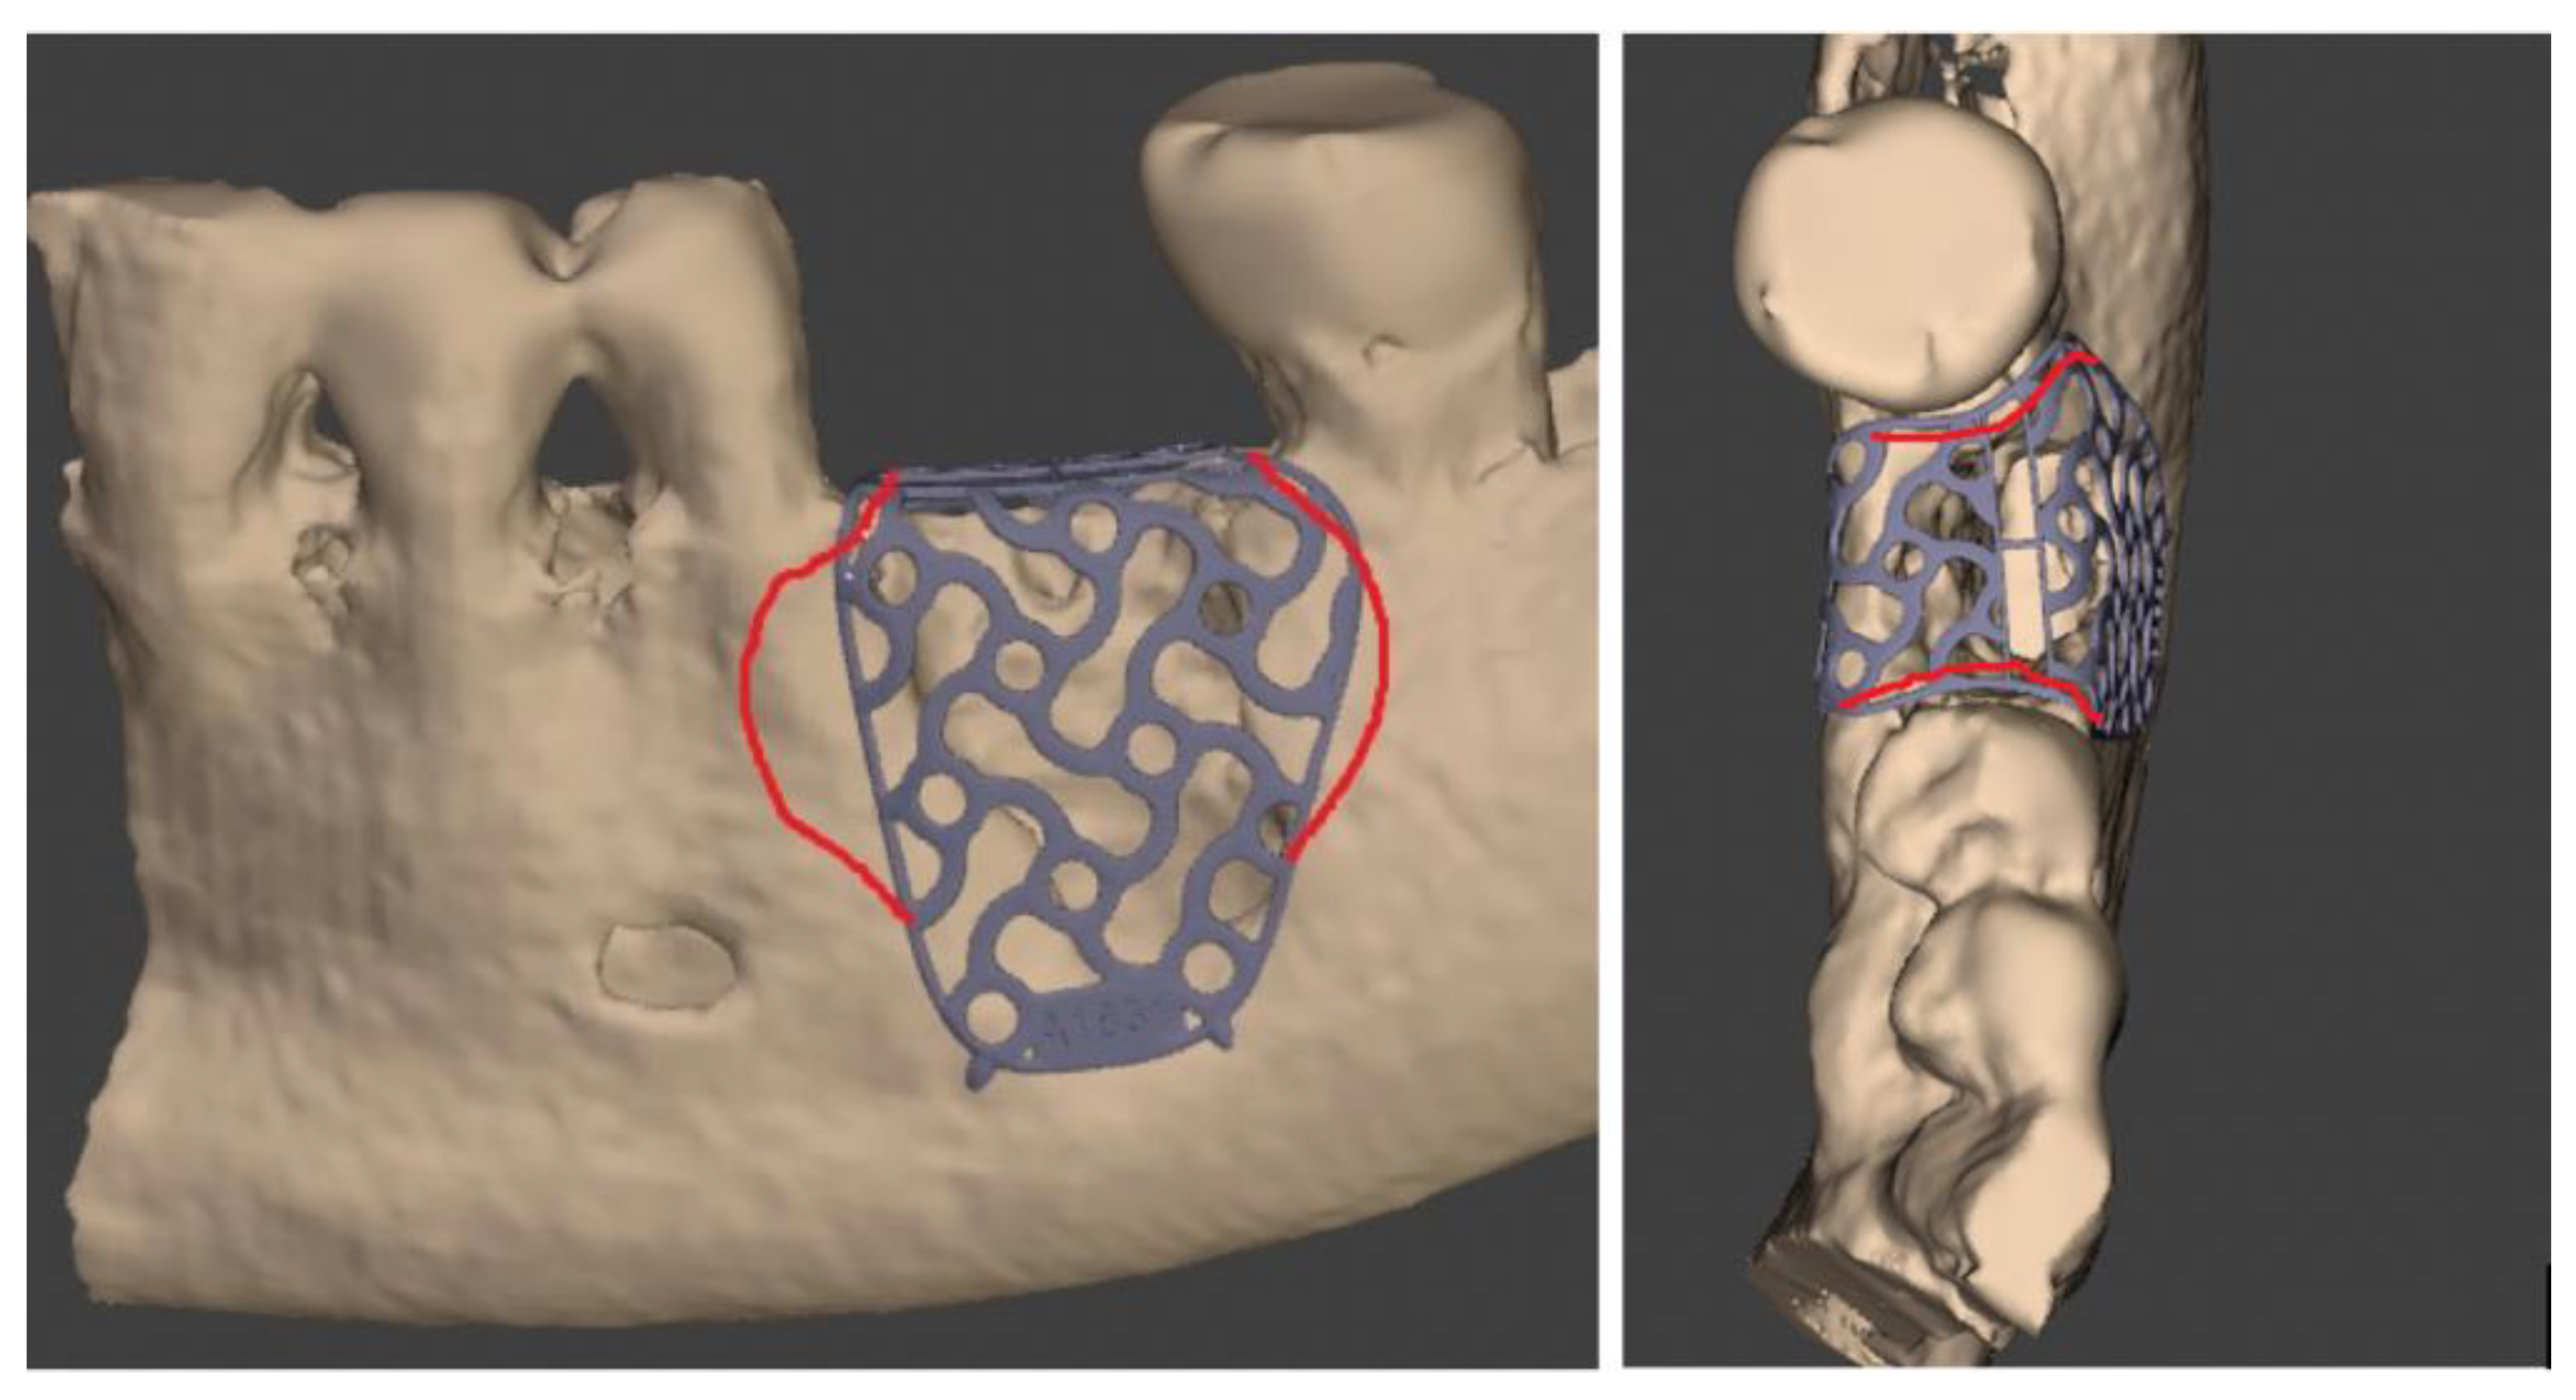

After that, through other dedicated software (Exocad GmbH-specific tool “cross section view”), it was possible to superimpose T0 e T1 CBCT scans to trace and evaluate the linear maximum vertical and horizontal gains for all the patients (in mm) and bone volume gains for all the grafted sites (in mm3) (Figure 6 and Figure 7).

Figure 6.

Segmentation of Dicom file and (T0–T1) CBCT superimposition to evaluate horizontal, vertical and bone volume gains.

Figure 7.

Segmentation of Dicom file and (T0–T1) CBCT superimposition to evaluate horizontal, vertical and bone volume gains for upper jaw case.